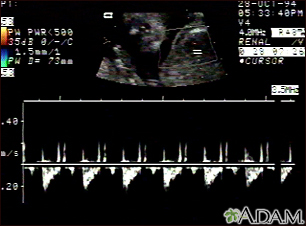

Ultrasound, normal fetus - heartbeat

This is a normal fetal ultrasound showing one pattern of the fetal heartbeat. Some ultrasound machines have the ability to focus on different areas of the heart and evaluate the heartbeat. This is useful in the early diagnosis of congenital heart abnormalities.